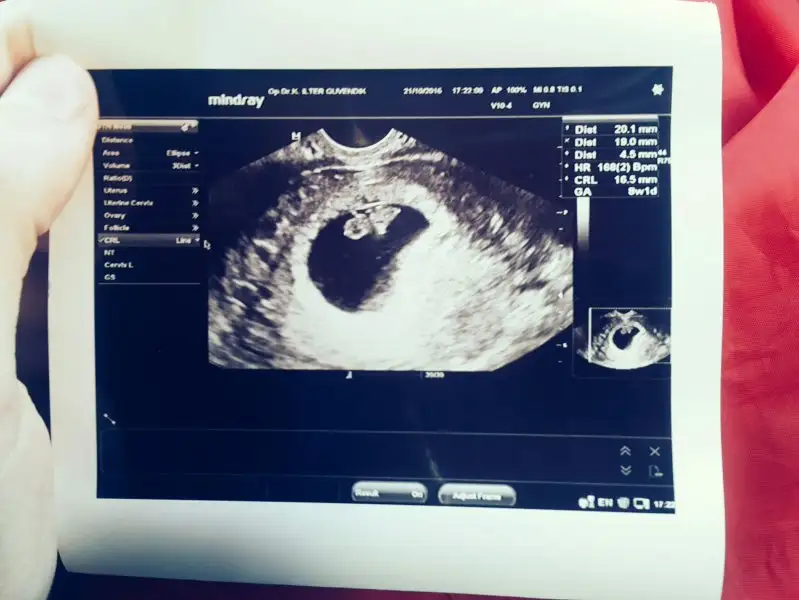

maşallah çok sevindim hepimiz iyi haberler alırız inşallaaahhh. :) benim profıldekı bebeğim 8+4 deki hali. şimdi 11 haftalık nasıl oldu kımbılır diğer kontrol 20gün sonra. :) :)İşte geldim. Söz verdiğim gibi artık kafaya takip strese girmiyorum. Bebeğim oldukça sağlıklı. 16.5 mm yani 17 mm olmuş bile çoktan. Kolları bacakları tohum tohum olmuş büyümek uzerelermis. Plesanta oluşmaya başlamış. 167 attı kalbi bu seferde. Artık bildiğiniz bebeğe benzemeye başlamış. 1 ay sonra çağırdı kontrole. 1 ay boyunca çok özleyeceğim bebeğimi orası kesin. İşte bizde havadisler böyle. Çok mutluyum ve yavrumun benimle olmasına da ayrıca mutluyum ❤

Ya nasıl geçer o kadar zaMan ki :) çok özler insan valla :) umarım arkadaşım umarım. Sen Şimdi gittiğinde cinsiteyi de öğrenirsinmaşallah çok sevindim hepimiz iyi haberler alırız inşallaaahhh. :) benim profıldekı bebeğim 8+4 deki hali. şimdi 11 haftalık nasıl oldu kımbılır diğer kontrol 20gün sonra. :) :)